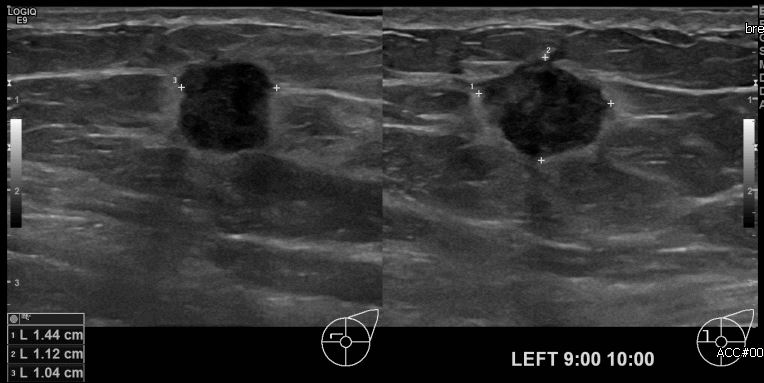

상기환자 건강검진상 이상소견으로 내원하신 60대 여성분으로 좌측 유방 9시에서

10시 방향에 의심스러운 멍울 조직검사 시행하여 좌측 침윤성 유관암 진단되었습니다.